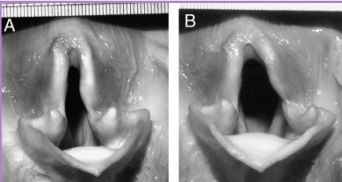

Laryngeal Paralysis

Et: arytenoid cartilages fail to abduct (recurrent laryngeal n. & Cricoarytenoideus dorsalis muscle)

Congenital, idiopathic, trauma, systemic dz, iatrogenic

Sig: Lg breeds - unilateral then progresses to bilateral

Cs: progressive signs, inspiratory stridor, voice change, exercise intolerance, cough/gag, anxiety, collapse

Dt: BW, Rads, neuro exam, laryngeal exam under light anesthesia(ready to do sx)

Abduction of arytenoids and vocal folds on inspiration

Tx: unilateral arytenoid lateralization (reduce obx and resistance) tie back

Prognosis is good, life-long aspiration risk, heat intolerance, Progression of polyneuropathy – if GOLPP is present